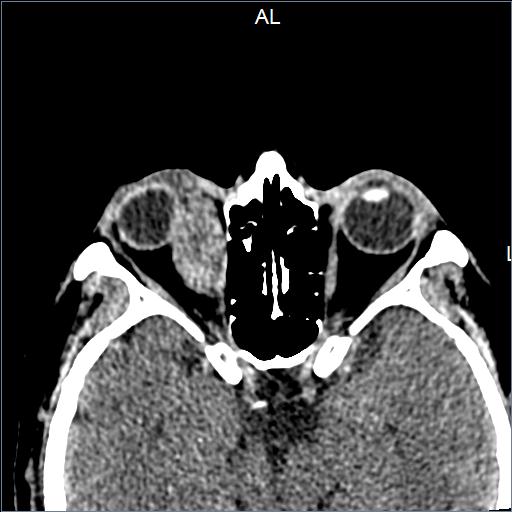

Padecimiento actual de 2 años de evolución caracterizado por sensación de cuerpo extraño, epífora y proptosis en ojo derecho.

A la exploración física con limitación a levoducción e infraducción en ojo derecho

Se realizaron estudios de imagen que detectaron tumor en órbita.